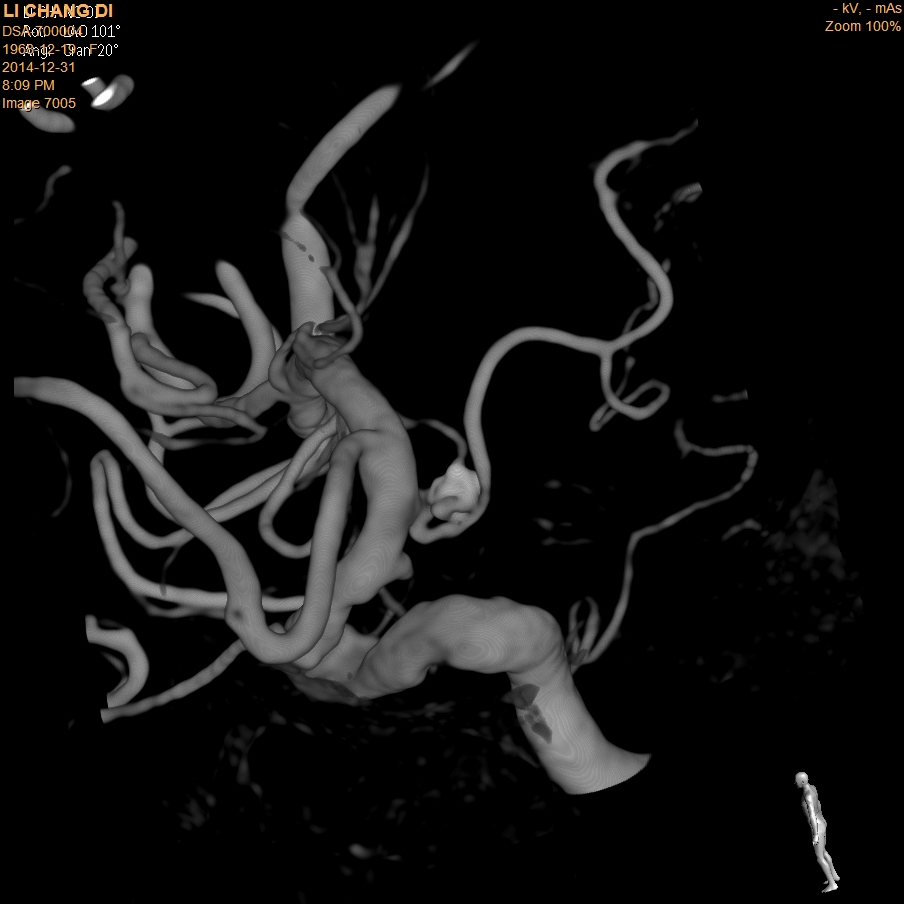

3.神经介入治疗:脑动静脉畸形、脑膜动静脉瘘、脑动脉瘤、脑动脉血栓溶解、脑膜瘤、颈动脉海绵窦瘘等微创介入治疗。

图左:病患右颈内动脉造影显示大脑中动脉有动脉瘤 右侧颈内动脉动脉瘤(红色箭头)

图右:经弹簧圈栓塞后,动脉瘤萎缩消退